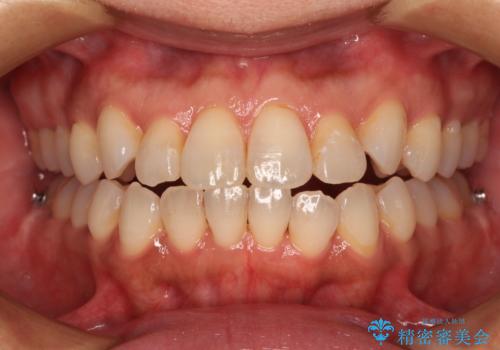

前歯のクロスバイト インビザラインによる矯正治療

- 上下のクロスバイトと前歯のデコボコを気にして来院された患者様です。

インビザラインを用い、IPR(歯と歯の間を削る)と歯列全体を拡大させることで、歯並びを整えていくこととしました。